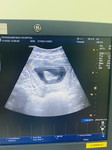

ท้อง6เดือนกว่าเลือดกำเดาชอบไหล

ท้อง6เดือนกว่าแล้ว เลือดกำเดาชอบไหล ไหลวันละรอบ-2รอบ แบบนี้มีความผิดปกติอะไรหรือเปล่าคะ